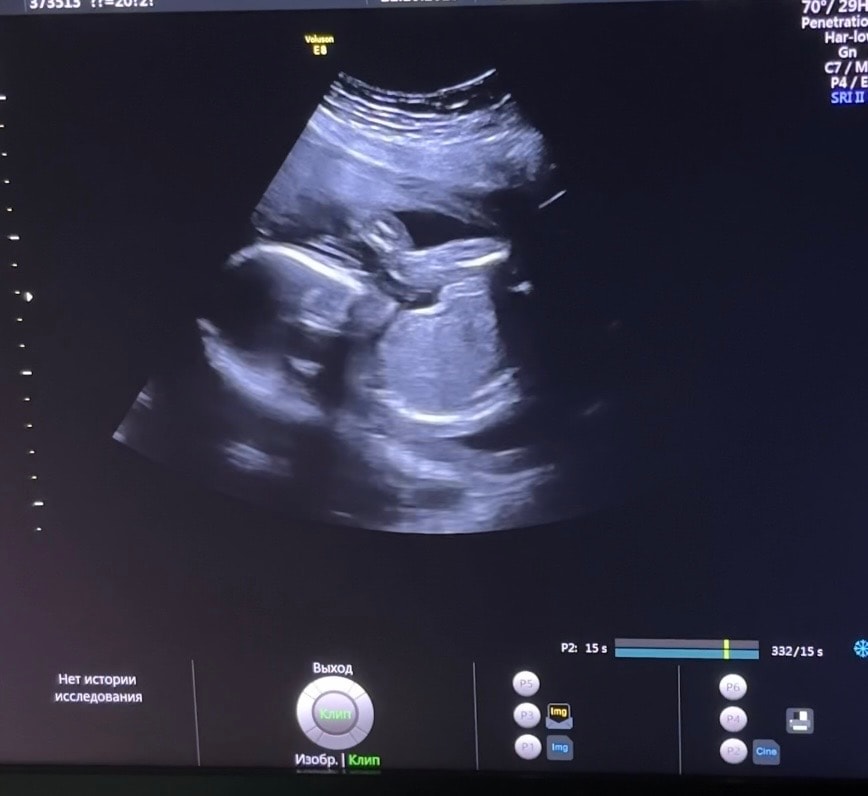

Наши будни, наши неделькиА так же второй скрининг, малышка развивается хорошо, отклонений никаких не выявлено. На втором скрининге сказали, что будет крупной, длинноногой( есть в кого😅). Места ей конечно не хватает , лежит ножками к личику. Недельки летят со скоростью света, всё таки вторая беременность с маленьким ребенком совсем незаметно проходит, помню с Верой очень медленно время тянулось, а тут особо и не заскучаешь😄По самочувствию всё отлично, живота по прежнему не видно, за последние 1.5месяца прибавила 1 кг, итого от начального веса который составлял аж 86 кг (минус 5.5 кг) надеюсь тенденция продолжится и за всю беременность наберу не более 10 кг😅 С первой дочкой я в этих неделях была +8кг и весила 89, и за всю беременность набрала 21 кг. Поэтому совсем не хочется идти рожать в весе 100+🤣